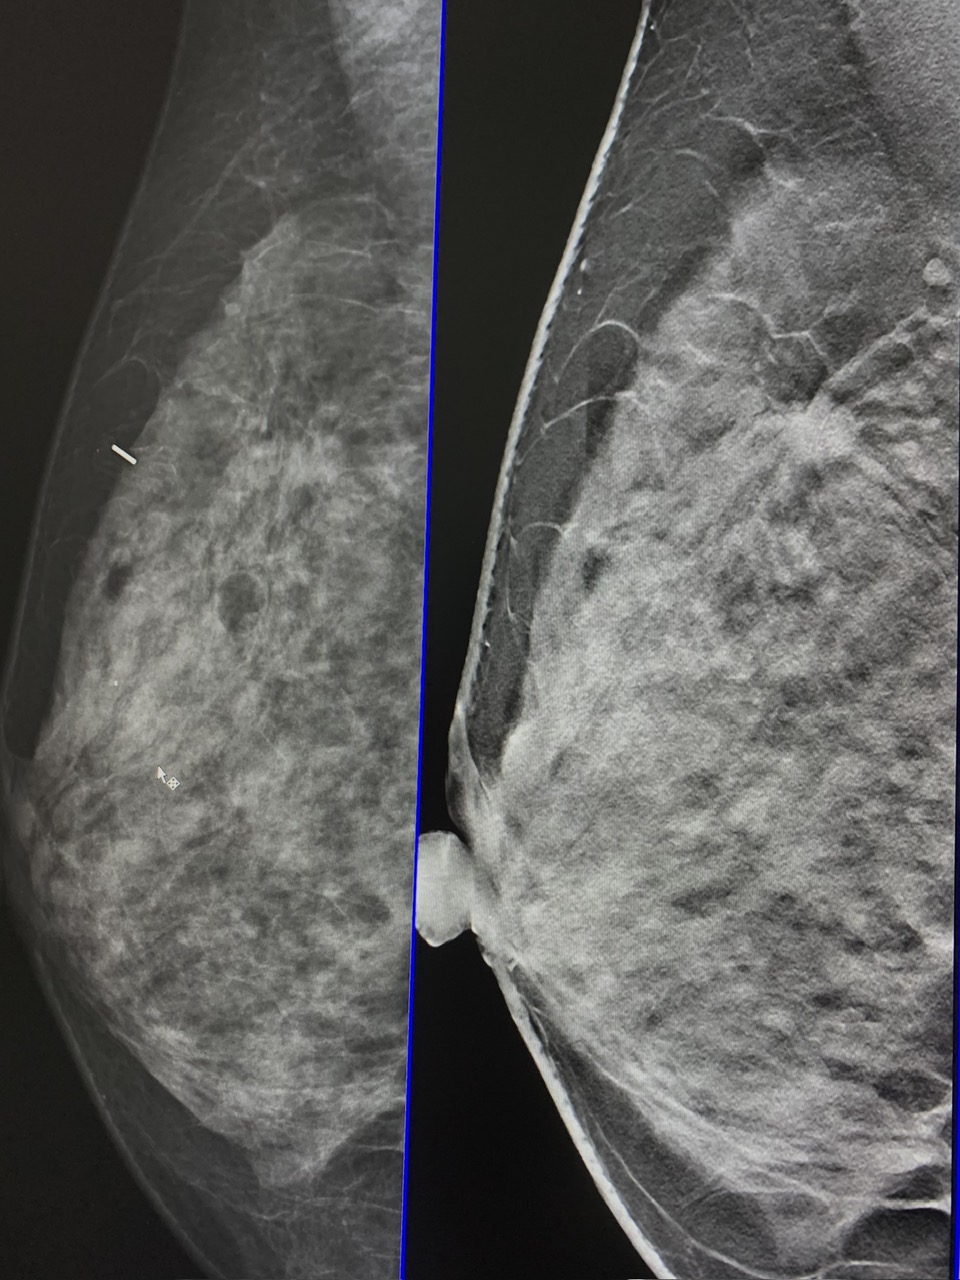

Chụp X-quang vú (Mammography) là phương pháp sử dụng tia X liều thấp để tạo ra hình ảnh chi tiết của mô tuyến vú. Đây là kỹ thuật được coi là “tiêu chuẩn vàng” trong tầm soát ung thư vú, đặc biệt đối với phụ nữ từ 40 tuổi trở lên.

Trong khi siêu âm vú thường phù hợp với phụ nữ trẻ có mô vú dày, thì chụp X-quang vú lại có ưu thế trong việc phát hiện vi vôi hóa – dấu hiệu sớm của ung thư vú mà siêu âm khó nhận diện.

Hình ảnh từ chụp X-quang vú giúp bác sĩ phát hiện:

Vi vôi hóa: Dấu hiệu sớm nhất của ung thư vú.

Khối u: Vị trí, kích thước, bờ viền.

Tổn thương lành tính: Nang, u xơ, thay đổi mô mỡ.

Dấu hiệu bất thường khác: Thay đổi cấu trúc mô vú, hạch vùng nách.

Kết quả thường được phân loại theo hệ thống BI-RADS, từ đó bác sĩ sẽ đưa ra hướng xử trí tiếp theo: theo dõi, làm thêm siêu âm vú, sinh thiết hoặc đưa vào chương trình tầm soát ung thư vú.